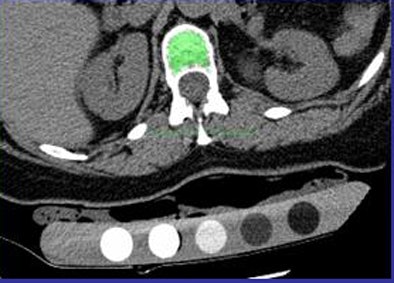

![]() |

| Automated BMD software automatically identifies the spinal region and labels L1 and L2 vertebral bodies, segmenting them automatically. Mathematical erosion is applied to remove the cortical bone. Mean CT values are then computed within the region, and the mean of L1 and L2 CT attenuation used to compute BMD. |